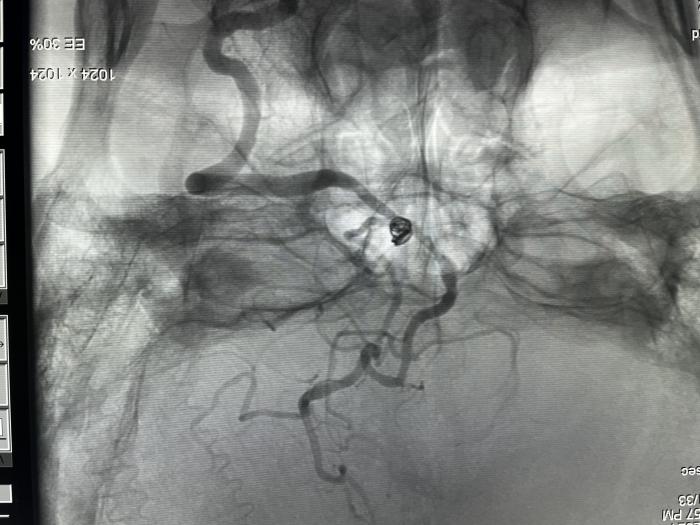

家住嘉禾县普满乡的雷女士今年61岁,因反复头痛头晕3年余,再发加重1天入院,既往有高血压、冠心病、脑梗死等多种病史,多次行头颅MRI+MRA检查提示,左侧椎动脉V4段不规则动脉瘤。但由于患者双侧髂动脉闭塞、左侧椎动脉开口处中度狭窄、左侧椎动脉V4段远端重度狭窄、瘤颈口发出支位于小脑后下动脉等情况,手术难度大,风险极高,稍有不慎可导致左侧小脑后下动脉闭塞,出现灾难性后果,并且患者双侧髂动脉闭塞,无法行常规股动脉途径治疗。

神经内一科团队立即组织多学科讨论,决定采用最新的手术方式,经左侧桡动脉行经导管颅内动脉瘤支架辅助栓塞术。神经内一科主任何劲松介绍,这种手术是通过密网支架改变血流导向,既能改善远端血管狭窄,又能保全左侧小脑后下动脉,并有效栓塞动脉瘤。“若采用传统弹簧圈栓塞/支架辅助弹簧圈栓塞,操作复杂,短期效果满意,但是术后复发风险较高。”何劲松说,“采用经左侧桡动脉入路行介入手术治疗,通过左侧桡动脉为动脉入路位点进行穿刺,该穿刺术不影响患者肢体的活动,跟平时桡动脉采血穿刺点类似,术后可随意行走,穿刺部位压迫时间短,舒适程度高,减少了因传统经股动脉穿刺行介入手术导致的穿刺部位血肿或假性动脉瘤,术后恢复更快。”

取得家属同意后,医务人员为患者取左侧桡动脉为入路,穿刺置鞘,予支架辅助下顺利实施了动脉瘤栓塞术,术后患者生命体征平稳,平安返回监护室观察。